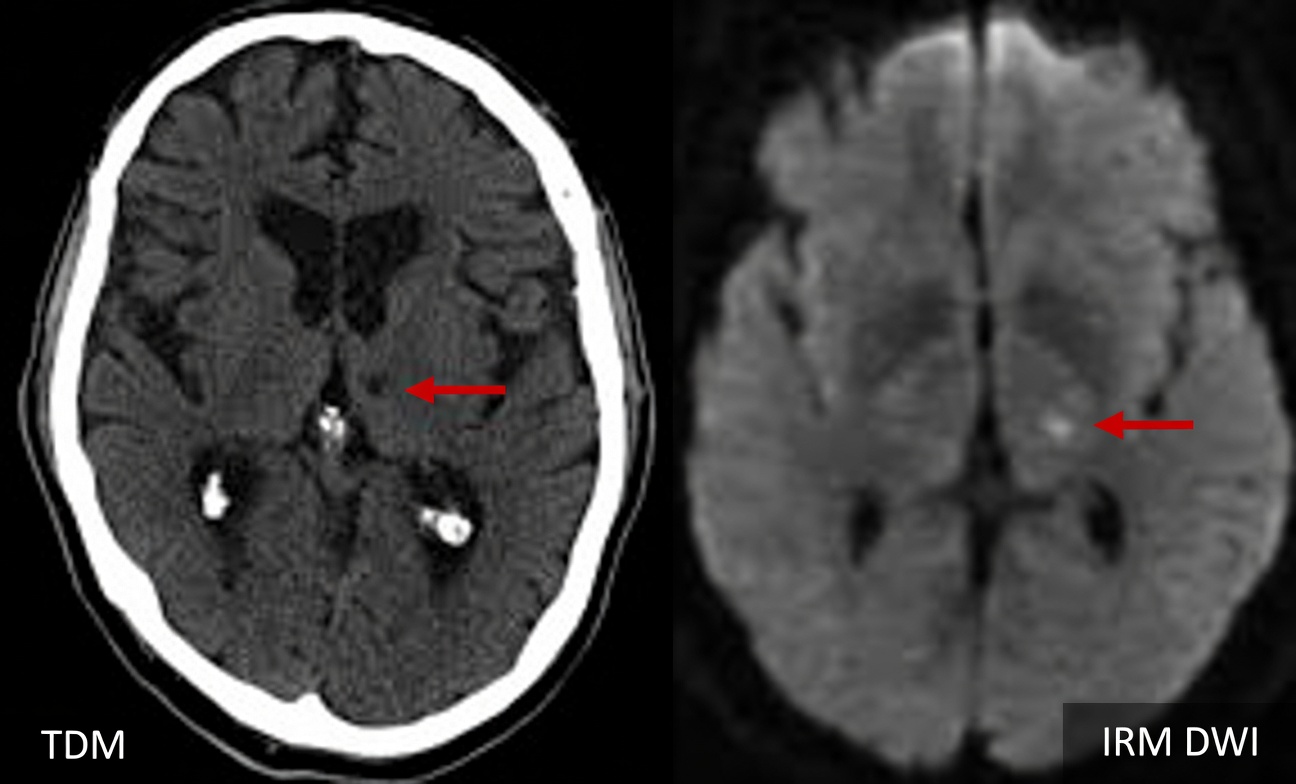

Imagerie cérébrale

- AVC lacunaire : petites cavités, atteinte de la substance blanche

- Vieillissement normal : changements minimes

- Autres causes : profils différents (atrophie, plaques, etc.)